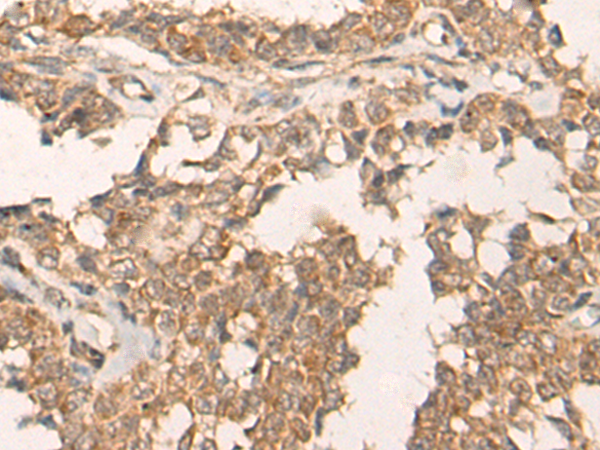

IHC positive control: |

Human ovarian cancer |